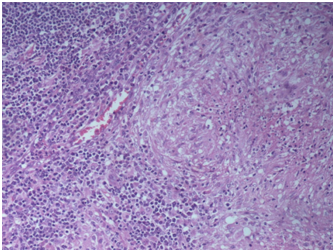

CECT chest and abdomen revealed nodular infiltrates with fibrotic bands in apical segment of right upper lobe with few rim enhancing necrotic lymph nodes at pre-tracheal, right para-tracheal, pre carinal and sub carinal region. Bone marrow examination was done which was normal. Lymph node biopsy of pre-tracheal nodes was done which showed caseous necrosis and langhans type giant cells (Figure 3).

Figure 3 Lymph node biopsy of pre-tracheal nodes was done which showed caseous necrosis and langhans type giant cells.